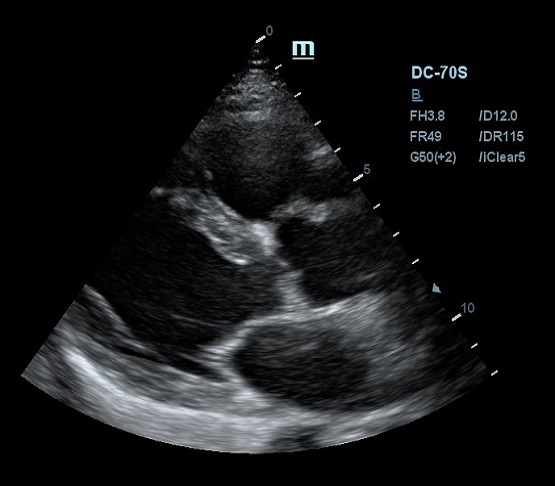

Благодаря постоянным инновациям, компания Mindray внедрила технологию iClear (адаптивная обработка изображений). Спекл - артефакт визуализации в виде акустического пятна - был препятствием для дифференциации структуры исследуемой ткани. iClear реализует агрессивное подавление спекл-паттернов, позволяя четко визуализировать анатомическую структуру на ультразвуковых изображениях. За счет уменьшения спекл-шума достигается лучшая дифференцировка тканей. Повышается контрастное разрешение без ущерба для пространственного разрешения. Уровень подавления спеклов можно выбрать под свои задачи, достаточно нажать кнопку или повернуть ручку, остальное сделает программный алгоритм.